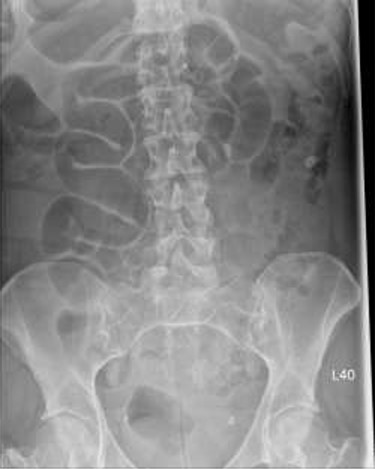

Patient initially diagnosed as biliary colic and surgical team had been contacted. Plain Abdominal radiograph showed dilated small bowels loops (Fig. 1). Chest radiograph revealed air under right hemi-diaphragm (Fig. 2). CT scan was done in emergency department and confirmed interposition of bowel between the diaphragm and the liver with a vascular/mesenteric pedicle swirl suggestive of malrotation or volvulus of the right colon. There was marked mural thickening and bold dilatation with high attenuation mucosa in keeping with closed loop obstruction and possible necrosis (Figs 3 and 4).

Chest X-ray shows air under diaphragm due to Chilaiditi syndrome.

Although an abdominal X-ray can be helpful in terms of diagnosis but not in all conditions, CT scan is an investigation of choice for such cases of caecal volvulus to make solid diagnosis and operate based on that evidence. In our patient the caecum, ileum and ascending colon were found entrapped and twisted at right hepato-diaphragmatic space resulting in an unusual Chilaiditi syndrome; hence a chest X-ray may give false impression of bowel perforation. Therefore, clinical correlation is always mandatory in order to consider different management options as in such cases.